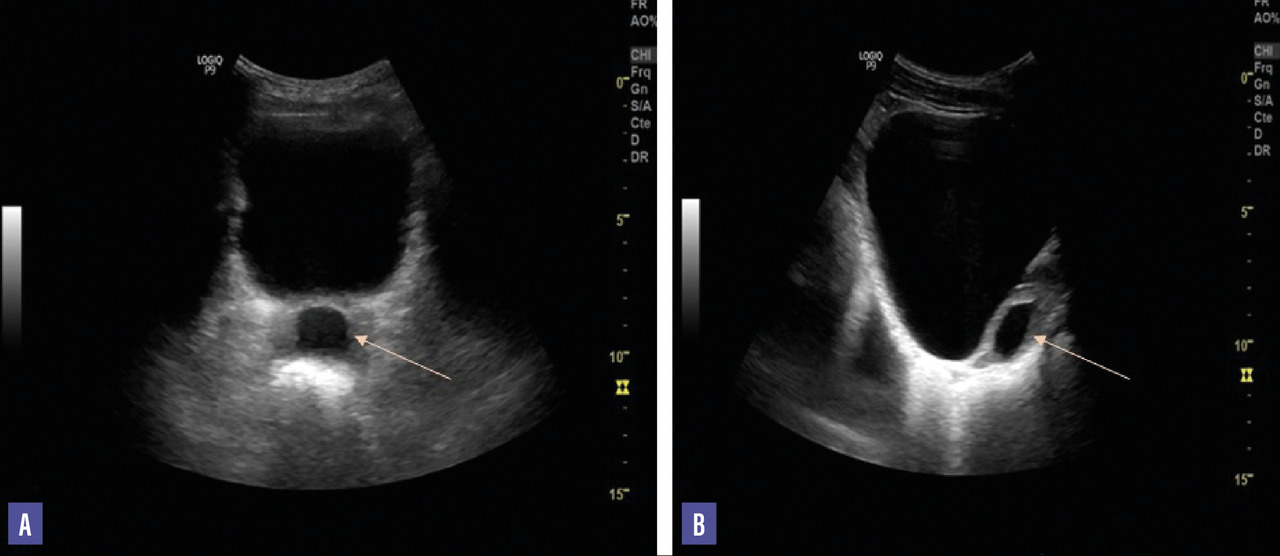

L’échographie sus-pubienne révèle une prostate de taille normale avec présence d’une formation kystique liquidienne anéchogène à paroi régulière mesurant 30 × 20 mm, enchâssée dans le tissu prostatique et se projetant sur la ligne médiane (fig. 1). L’échographie prostatique représente l’élément clé pour le diagnostic du kyste chez ce patient.

L’échographie prostatique par voie sus-pubienne ou endorectale a un double intérêt diagnostique et thérapeutique, avec la ponction-aspiration du liquide intrakystique. Elle est un examen essentiel pour la classification des kystes prostatiques. En effet, les kystes d’origine müllérienne apparaissent comme une image liquidienne anéchogène à paroi régulière, de topographie médiane intraprostatique. Les kystes des canaux éjaculateurs sont de topographie médiane et légèrement latéralisée et se projettent sur le trajet du canal éjaculateur.4